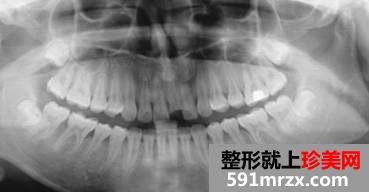

这是医生给我照的。说我这口腔卫生状态也不太好,可是我平时挺注意口腔清洁的。唉。。。。。